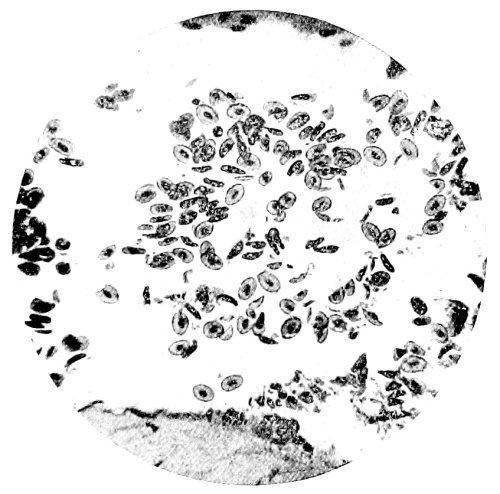

8. Measurement of Blood Corpuscles (human) 97

9. Measurement of Blood Corpuscles (sheep) 97

10. Photo-micrograph of Red Blood Corpuscles from Domestic Fowl 99

11. Photo-micrograph of Blood Corpuscles of Fish 99

12. Photo-micrograph of Blood Corpuscles from a Dried Stain of the Blood of a Cod-fish 100

13. Photo-micrograph of a Frog‘s Blood showing oval nucleated Red Corpuscles 101

14. Photo-micrograph of Crystals of Hæmin 102